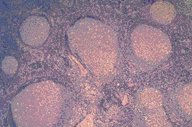

Follicular hyperplasia

This is a very low power H&E stained view of a

lymph node showing marked follicular hyperplasia.

Both central and cortical areas are markedly

hyperplastic in terms of cell number and follicles.